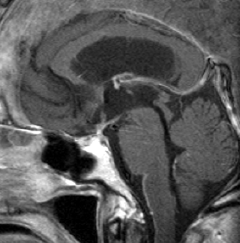

7歳の子が視力障害で発症しました。両耳側半盲という症状です。典型的な鞍隔膜下頭蓋咽頭腫です。ガドリニウム造影剤を入れないMRIでみえる,黄色い矢印の先の白い高信号は抗利尿ホルモンです。ですから下垂体機能もまだ残っていて,尿崩症はありません。視力障害が戻らないことがあるのでなるべく早く,経鼻的な手術で摘出した方がいいものです,簡単 o(^-^)o